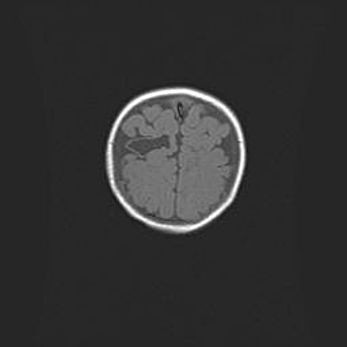

Наружная гидроцефалия с возможной атрофией височных областей.

Возраст: 28 дней

Вес: 3670 г

Пол: мужской

Окружность головы: 38 см

Срок гестации: 40 недель

Гидроцефалия головного мозга у новорожденных – это заболевание, которое характеризуется скоплением избыточного количества спинномозговой жидкости в желудочковой системе головного мозга в результате затруднения её перемещения от места выработки к месту поглощения в кровеносную систему или вследствие нарушения абсорбции. При открытой наружной форме гидроцефалии у новорожденных расширяются и переполняются субарахноидные пространства.

При нормотензивных  формах,  которые,  как  правило,  являются  следствием  перенесенных ишемических  повреждений  паренхимы  мозга,  возможно  сочетание микроцефалии  с нормотензивной гидроцефалией. В основе данных изменений лежит атрофия больших полушарий с преимущественной  локализацией  в  лобно-височных  областях.